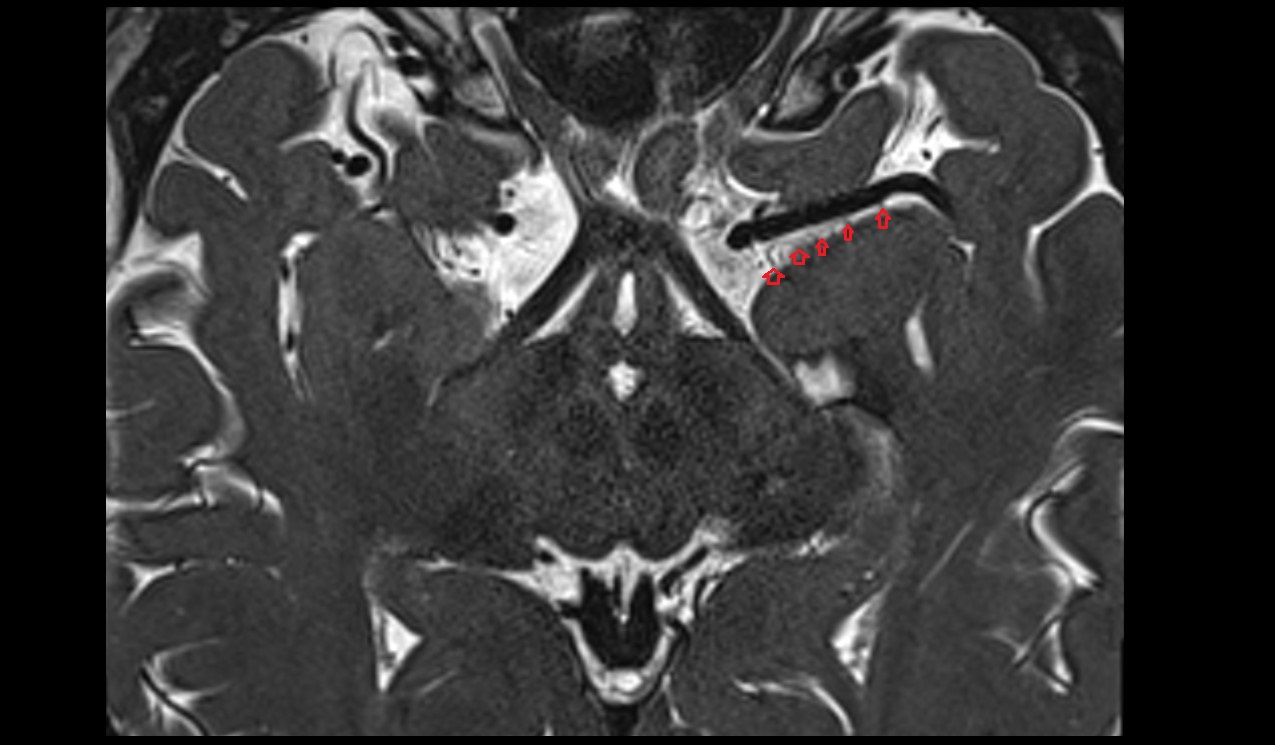

- Temporomandibular joint

- Articular disc of temporomandibular joint

- Mandibular condyle

- Mandibular fossa